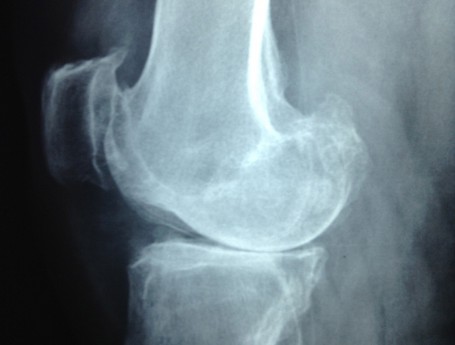

Revision Total Knee Replacement After Infection

• Revision Total Knee Replacement After Infection